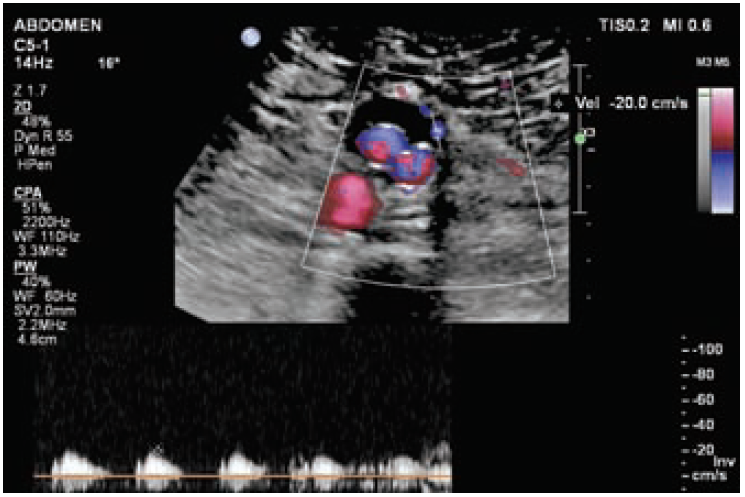

Рис. 1. Эндолик из нижней брыжеечной артерии.

По данным КТ сосудов брюшной полости с КУ: Состояние после эндопротезирования аневризмы инфраренального отдела аорты, подвздошных артерий. Эндолик II типа, вероятно из нижней брыжеечной артерии.

По данным ультразвукового исследования: Аневризматический мешок до 3,0 см. Визуализируется проходимый эндопротез. Ультразвуковые признаки эндолика II типа из нижней брыжеечной артерии (рис. 1, 2).

Рис. 2. Эндолик из нижней брыжеечной артерии.